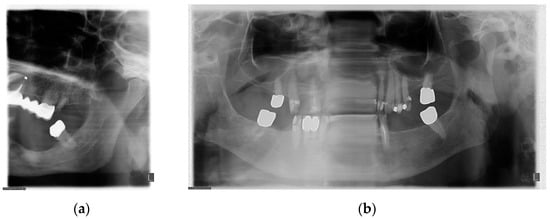

4. Frequency of Errors in PAN Performance and Interpretation

5. The Importance of Head Orientation